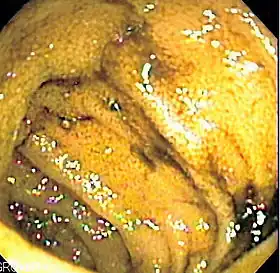

![]() Endoscopic image of normal small bowel | |